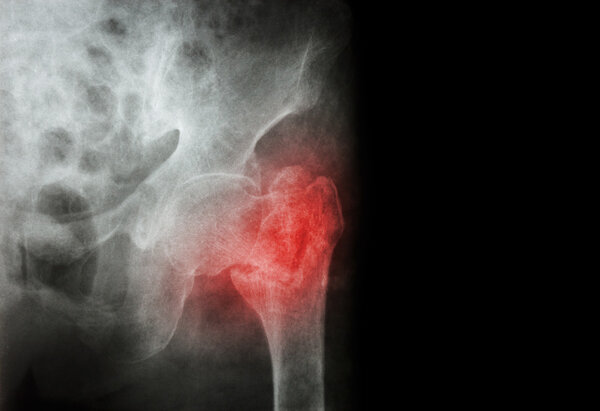

而股骨骨折,一般就是股骨遭受直接或间接暴力后,导致股骨的完整性破坏或连续性中段。最常见的原因就是暴力,比如车祸,比如滑雪摔倒,比如打架一棍子给抡骨折了,还有新闻中的这类不恰当的运动锻炼。

股骨骨折不仅可能造成患者难以言状的疼痛,严重时还可能因疼痛肿胀使患者的患肢完全丧失活动能力、出血过多休克从而危机生命安全。

股骨骨折以后,绝大多数情况下都需要手术,就像杨女士一样需要置入髓内钉,而且以后还得取出来。

如果因为就诊不及时、不正当治疗、内固定失效、未做好康复训练等,还可能会造成畸形愈合、肌肉萎缩、关节僵硬等问题。